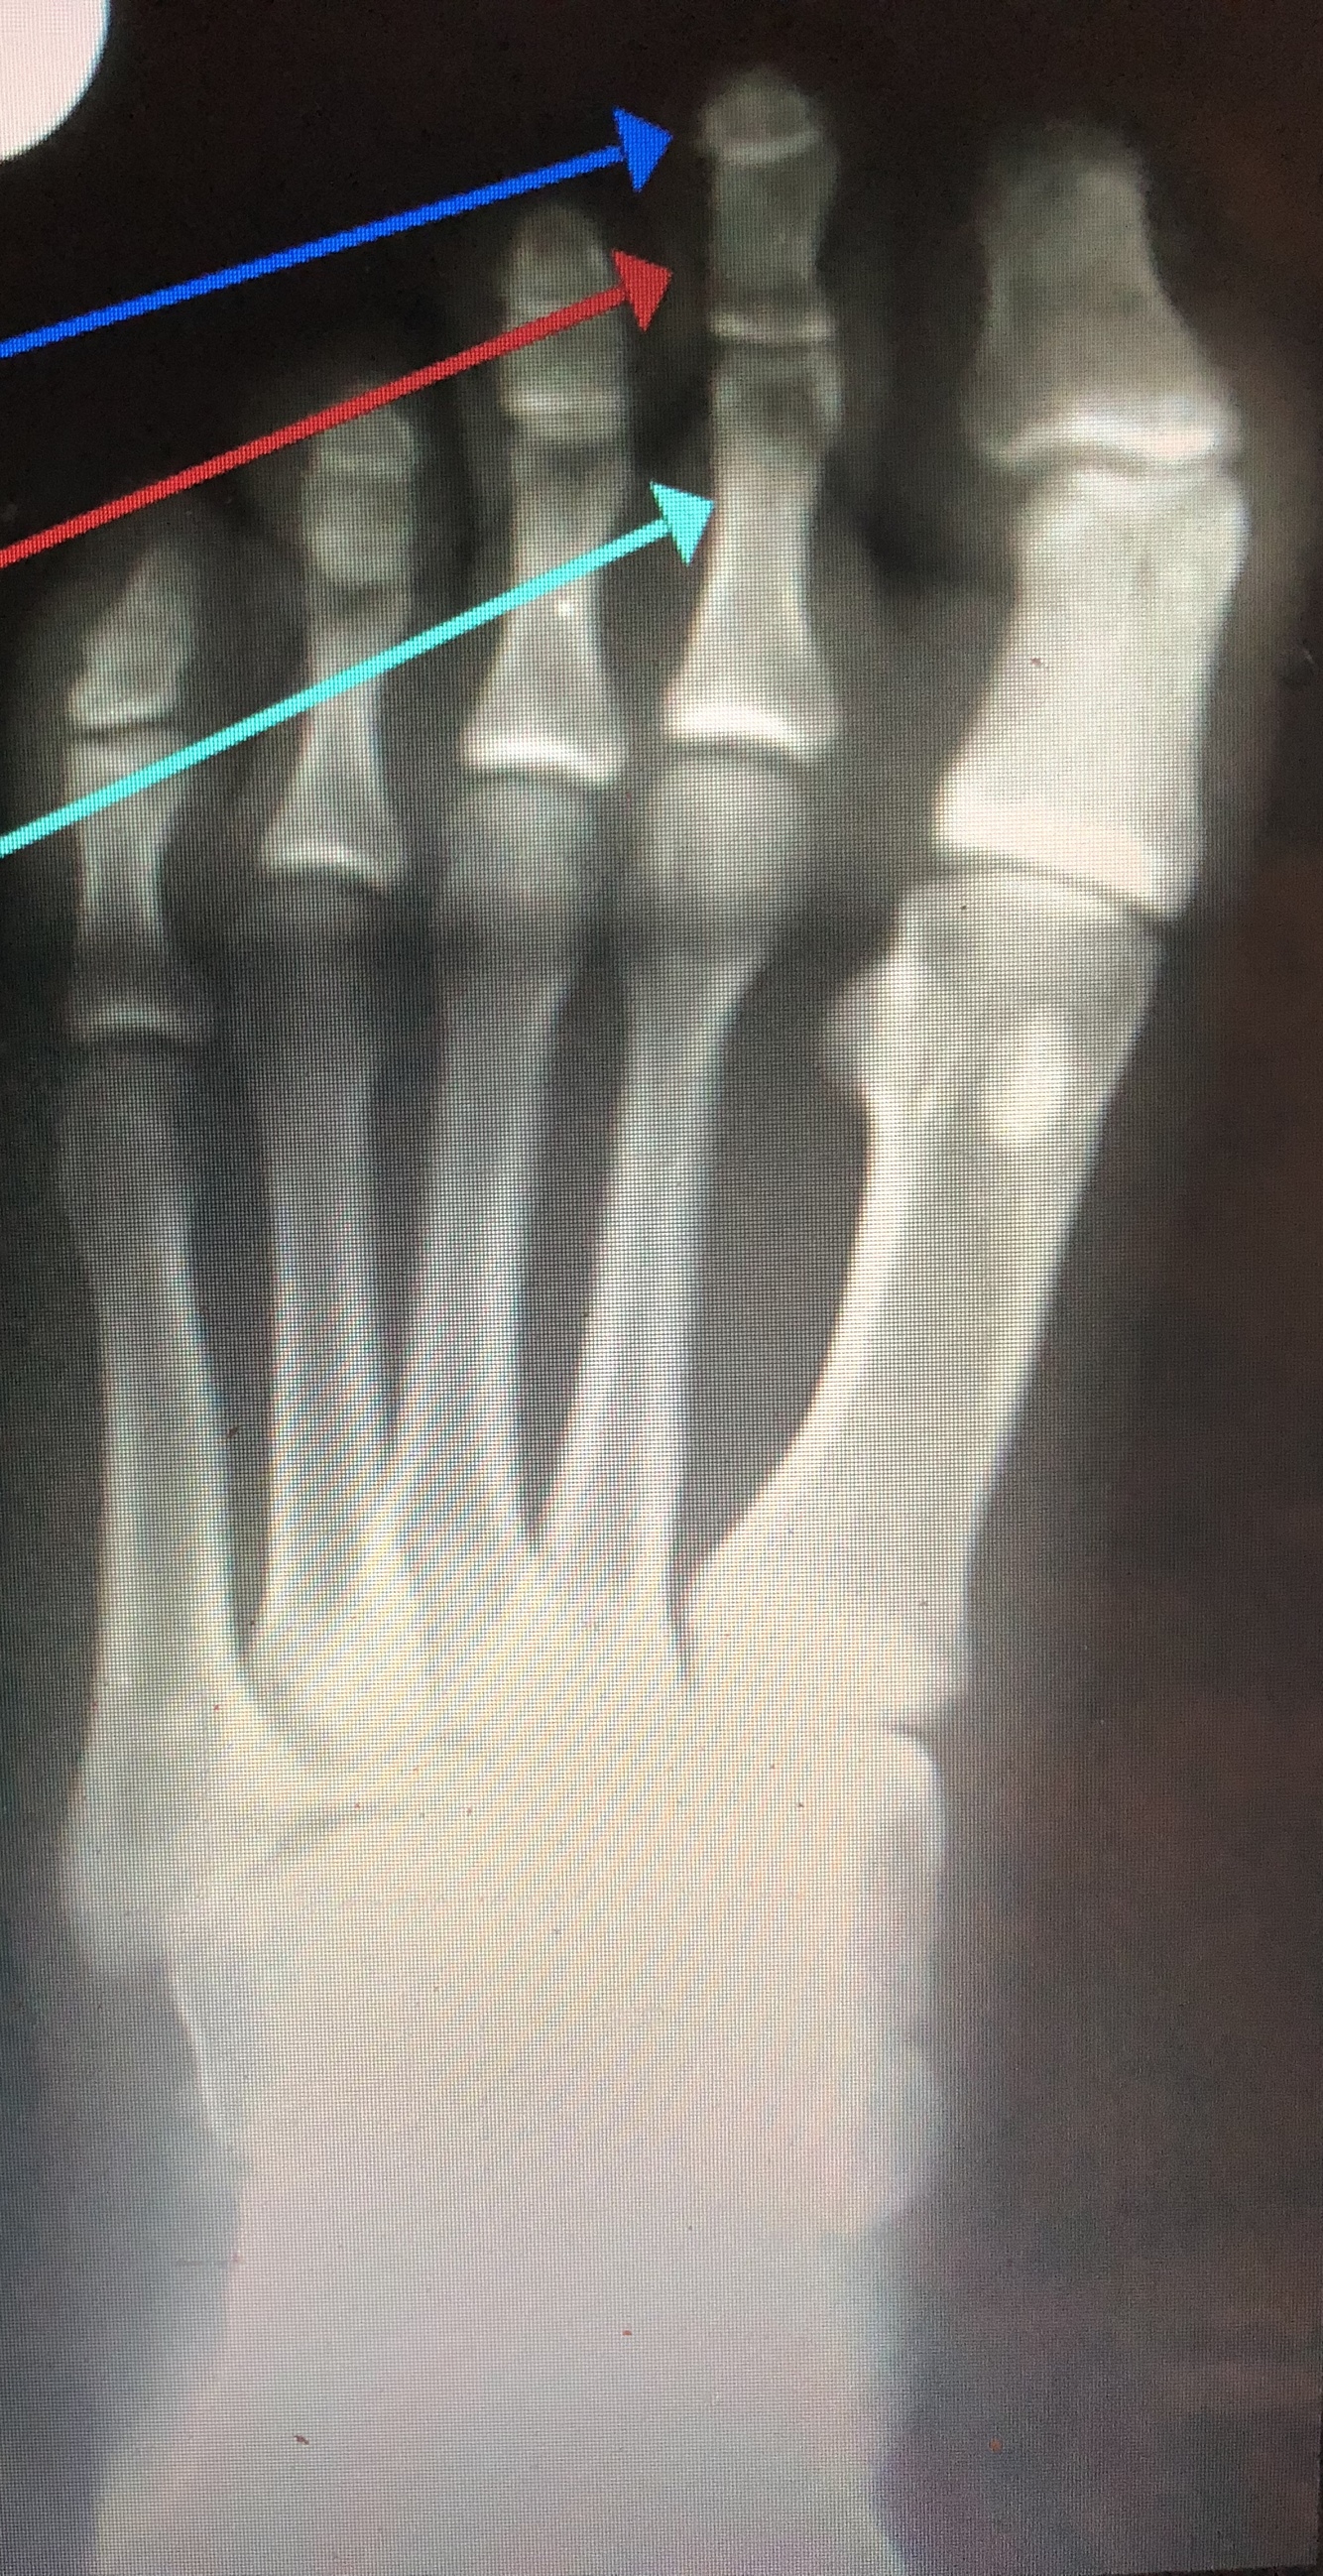

Which phalange is which color?

Dark blue - distal second phalange

Red - middle second phalange

light blue - proximal second phalange

What part of the phalanges are what color?

red - head of second phalange

dark blue - base of second phalange

light blue - Distal Ungual tuft